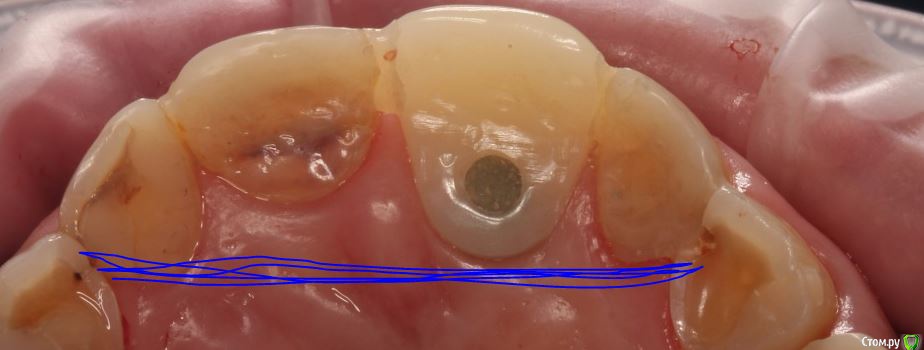

zubovolok Опубликовано 28 февраля, 2017 Автор Поделиться Опубликовано 28 февраля, 2017 Во-первых оттиск не точный с большим колличеством оттяжек как небно так и вестибулярно, сделать полноценную десневую маску не получится. Во вторых результат будет напрямую зависеть от глубины положения платформы имплантата, то есть чем глубже имплант тем лучше прогноз вывести корону в нормальную форму. Рекомендую сделать временную коронку и поиграться с ее формой, если потребуется сделать хирургическую коррекцию мягких тканей если понадобится с подсадкой. Думаю можно вполне получть что-то более менее приличное если конечно имплантат не стоит совсем уж поверхностно, да и с таковым и некоторые выкручиваются. Глубина 4-5 мм. Вопрос ещё что использовать стандартный 25 градусный или приливаемый (но получается кхс под десну)? Сам естественно понимаю что положение импланта неправильное и выходом будет переставить имплант. Но хотелось собрать мнения как можно ещё из неё выйти. Вестибулярно без подсадки если выводить, конечно будет затруднена гигиена, ещё больше смущает проблемы с дикцией когда коронка будет установлена. Язык долго привыкать будет к конструкции. Ссылка на комментарий

zubovolok Опубликовано 28 февраля, 2017 Автор Поделиться Опубликовано 28 февраля, 2017 На счет оттисков ответили Вам.Я имел ввиду небные поверхности зубов там ретейнер стоит, воском закрывал поэтому нечетко и с оттяжками. Ссылка на комментарий